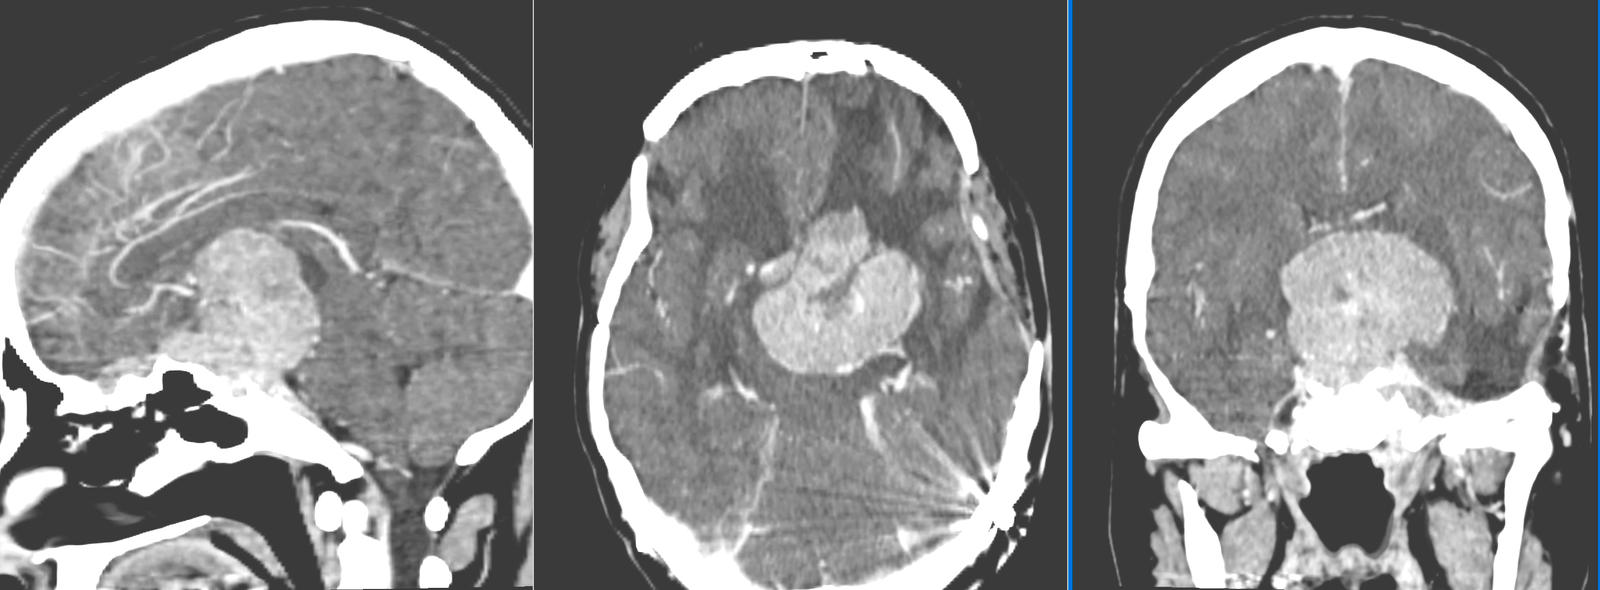

- CT – de obicei doar ca primă investigație. Meningioamele sunt vizibile mai ales la administrarea de substanță de contrast. Permite evidențierea afectării osoase (distrucție – osteoliză sau îngroșare – hiperostoză), a calcificărilor intratumorale precum și a rețelei venoase (angio-CT)

- Angiografia – meningioamele sunt intens vascularizate si se vad bine la o angiografie; în plus, această tehnică permite și embolizarea tumorii – reducerea semnificativă a vascularizației tumorale prin injectarea unui gel special, ceea ce reduce sângerarea intraoperatorie și permite o intervenție chirurgicală în condiții mult mai bune.

- RMN – cea mai completă investigație, oferă detalii despre relația cu țesutul cerebral, vasele de sânge și nervii Captarea substanței de contrast este deosebit de importantă.